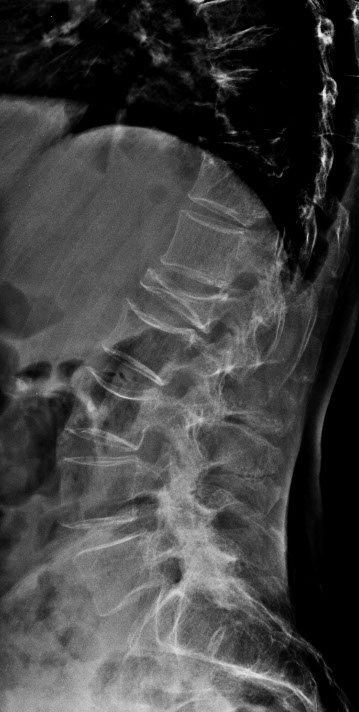

Osteoporose führt dazu, dass die Knochen porös und weniger belastbar werden. Die Folge sind Knochenbrüche auch ohne schwere äußere Krafteinwirkungen wie z. B. Stürze, Unfälle. Durch Osteoporose bedingte Knochenbrüche treten insbesondere in folgenden Skelettabschnitten auf:

• Wirbelsäule (sogenannter Fisch- und Kompressionswirbel)

Vor allem Wirbeleinbrüche werden von den Betroffenen oft nicht erkannt, die Folgen sind aber starke Rückenschmerzen, Verringerung der Körpergröße und die sogenannte Rundrückenbildung.